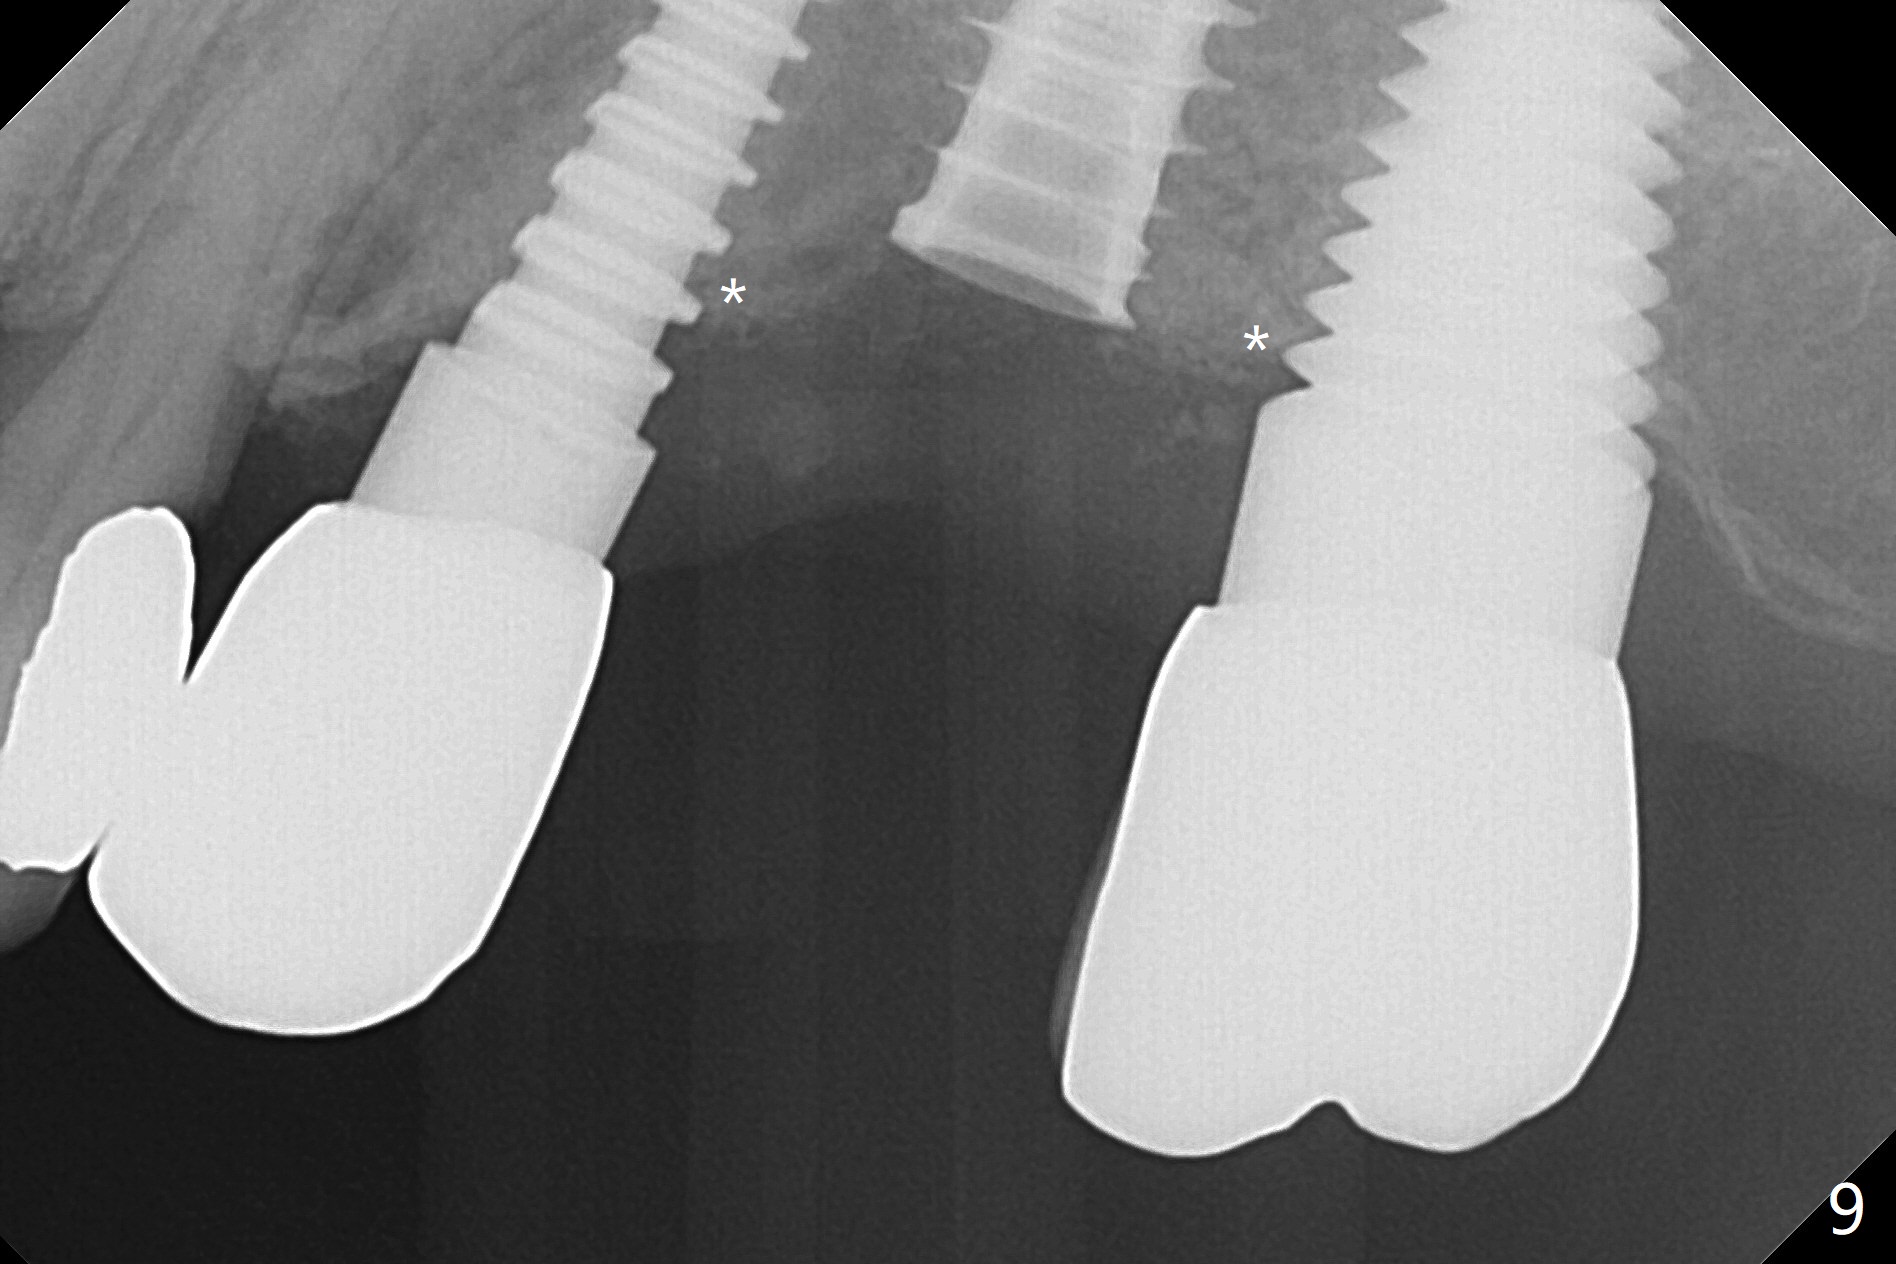

Initial osteotomy in the septum of the tooth #14 is 9 mm, approximately 2 mm from the sinus floor (Fig.1).  Subsequent osteotomy depth is 11 mm, followed by insertion of a 4.5x11 mm dummy implant (Fig.2).  After use of Magic Drill (MD) 4.8 mm for 9 mm, a 5x11 mm IBS implant is placed with sinus lift without additional bone graft (Fig.3 *).  In contrast, autogenous bone (from MD) and Vanilla Graft are meticulously placed in the remaining socket (+) before and after placement of a 6.5x5.7(2) mm abutment.  An immediate provisional is fabricated to close the sockets.  There is buccal tenderness 1-3 months postop.  There is distopalatal implant thread exposure.  A healing abutment (5.5x2 mm) is placed.  CT confirms thin buccal plate (Fig.4,5).  It appears that the implant should have been as palatal as possible.  The tenderness remains for the next 2 weeks.  When the healing abutment is removed, the implant seems to have been placed shallow, ~ 1 mm subgingival (Fig.6).  With local anesthesia, the implant is reversed to clean the coronal threads with Titanium brush and copious irrigation (Fig.7).  The implant is then placed ~4 mm subgingival (Fig.8) and slightly subcrestal (Fig.9,10).  It appears that the postop bone loss (Fig.9 *, as compared Fig.1,2) makes the implant look to be placed too shallow.  When the implant is being placed deeper, the buccal plate feels intact.  The early periimplantitis is apparently due to postop bone loss more than buccal placement, although certain degree of buccal bone resorption must occur.  A 6x4 mm healing abutment is placed.  Left facial swelling develops 2 days post implant elevation (Fig.11,12, as compared to preop (Fig.13)).  The left maxillary sinus cloud (Fig.12) appears to be a false positive finding, since the same feature exists prior to implant elevation (Fig.13).  Both sinuses look clear prior to implant elevation (Fig.14).  Amoxicillin switches to Augmentin and Flagyl, since the patient is reluctant to have the implant removed.  Finally the sinus infection is under control.  The patient feels left facial swelling 9 months postop (5 months post elevation) and reports left nasal discharge ~ 1 month earlier.  There is mild buccal plate tenderness.  The implant seems to be buccally placed (Fig.15,16), although there is no significant change radiographically (Fig.17).  The implant is removed with bone graft (Fig.18 *).  To avoid complication and failure, an immediate implant at the upper 1st molar should be short and placed deep.